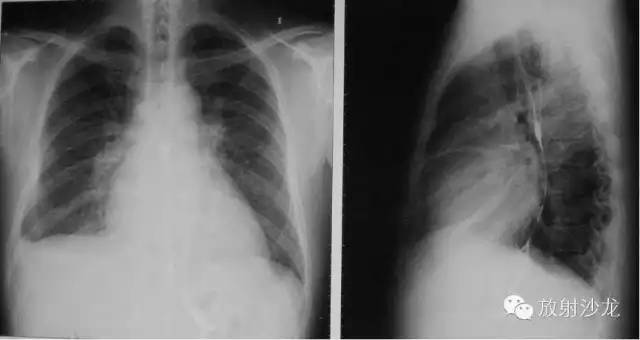

左房右室增大

X线表现为心脏增大,肺淤血,间实质肺水肿,胸腔积液

心 衰-心脏排血能力不足以维持人体正常生理功能。